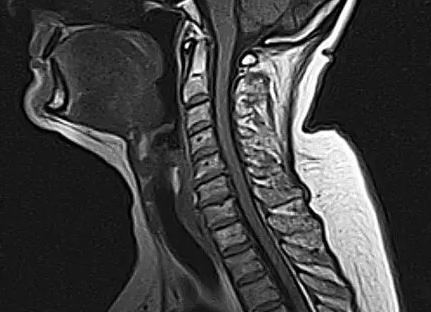

МРТ-снимок внутреннего уха

МР исследование полезно выполнять для обнаружения микроскопических отклонений тканей. Томограф образует несколько снимков, дающих возможность сформировать 3D модель. Обследование диагностирует различные трудно заметные нарушения структуры системы среднего, внутреннего уха.

Внутреннее ухо самое сложное по строению, называют его лабиринт, поэтому проводить диагностику должны отоларингологи. По форме напоминает улитку. О его состоянии можно судить по снимкам МРТ.

Что показывает МРТ среднего и внутреннего уха

МРТ уха абсолютно безопасна для здоровья человека и позволяет диагностировать практически любое заболевание органов слуха. Такой вид исследования как МРТ в силах определить самые незначительные отклонения в системе функционирования органов слуха. По снимкам МРТ внутреннего прохода уха можно выявить все подробности в трёхмерном измерении:

Что поможет выявить диагностика

Магнитно-резонансная томография области внутреннего уха позволяет на ранних стадиях выявлять самые незначительные изменения функций и структур здоровых органов головного мозга, находящихся в зоне расположения внутреннего уха. При проведении МРТ делается серия фотоснимков, которые демонстрируют специалистам срезы необходимого органа в разных проекциях. Плюсом данного вида обследования является тот факт, что затемненных областей при томографии не бывает, визуализировать возможно любой участок.

Также существует возможность создания 3D-модели рассматриваемого участка, который можно рассматривать под различными углами.

Томография позволяет выявить воспаления, локализованные на слуховом нерве пациента (кохлеарный неврит), невриному или опухоль на слуховом нерве, разрастание тканей, разрушение и деформацию костной ткани, метастазы, последствия перенесенных отитов или деформации лабиринта. Периферические лабиринтные расстройства принято медиками делить на невоспалительные и воспалительные, что влияет на выбор методики дальнейшей терапии.